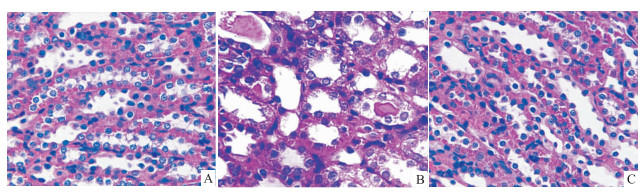

空白对照组的大鼠肾组织结构未见异常(Fig1A)。顺铂模型组的肾小管上皮细胞明显水肿、脱落,肾小管管腔狭窄,可见蛋白质或红细胞管型(Fig1B)。顺铂+PNS组的肾组织病理损害较顺铂模型组明显改善(Fig1C)。

|

| Fig 1 HE-staining of rat renal tissues in each group A:Control ;B:Cisplatin;C:Cisplatin+PNS. |